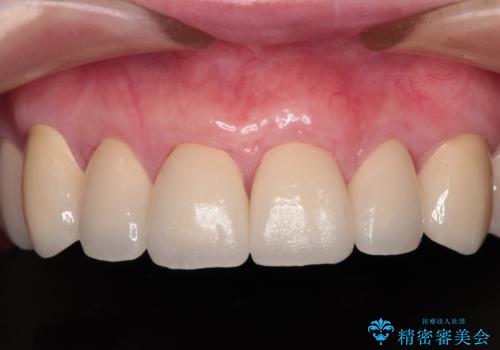

むし歯だらけの前歯をオールセラミッククラウンできれいに

全顎的にむし歯が多く、根管治療の必要奥歯や、審美的に気になっている前歯を中心にオールセラミッククラウンにて補綴治療を行うこととしました。

上顎前歯は歯肉退縮により歯根が露出していたため、事前に歯肉移植術により根面被覆を行い、その後にオールセラミッククラウンを装着することとしました。

歯肉移植術による根面被覆を行うかどうかは非常に悩まれていましたが、歯肉が覆われたことで長く見えていた歯の長さが整い、きれいな前歯の仕上がりとなりました。